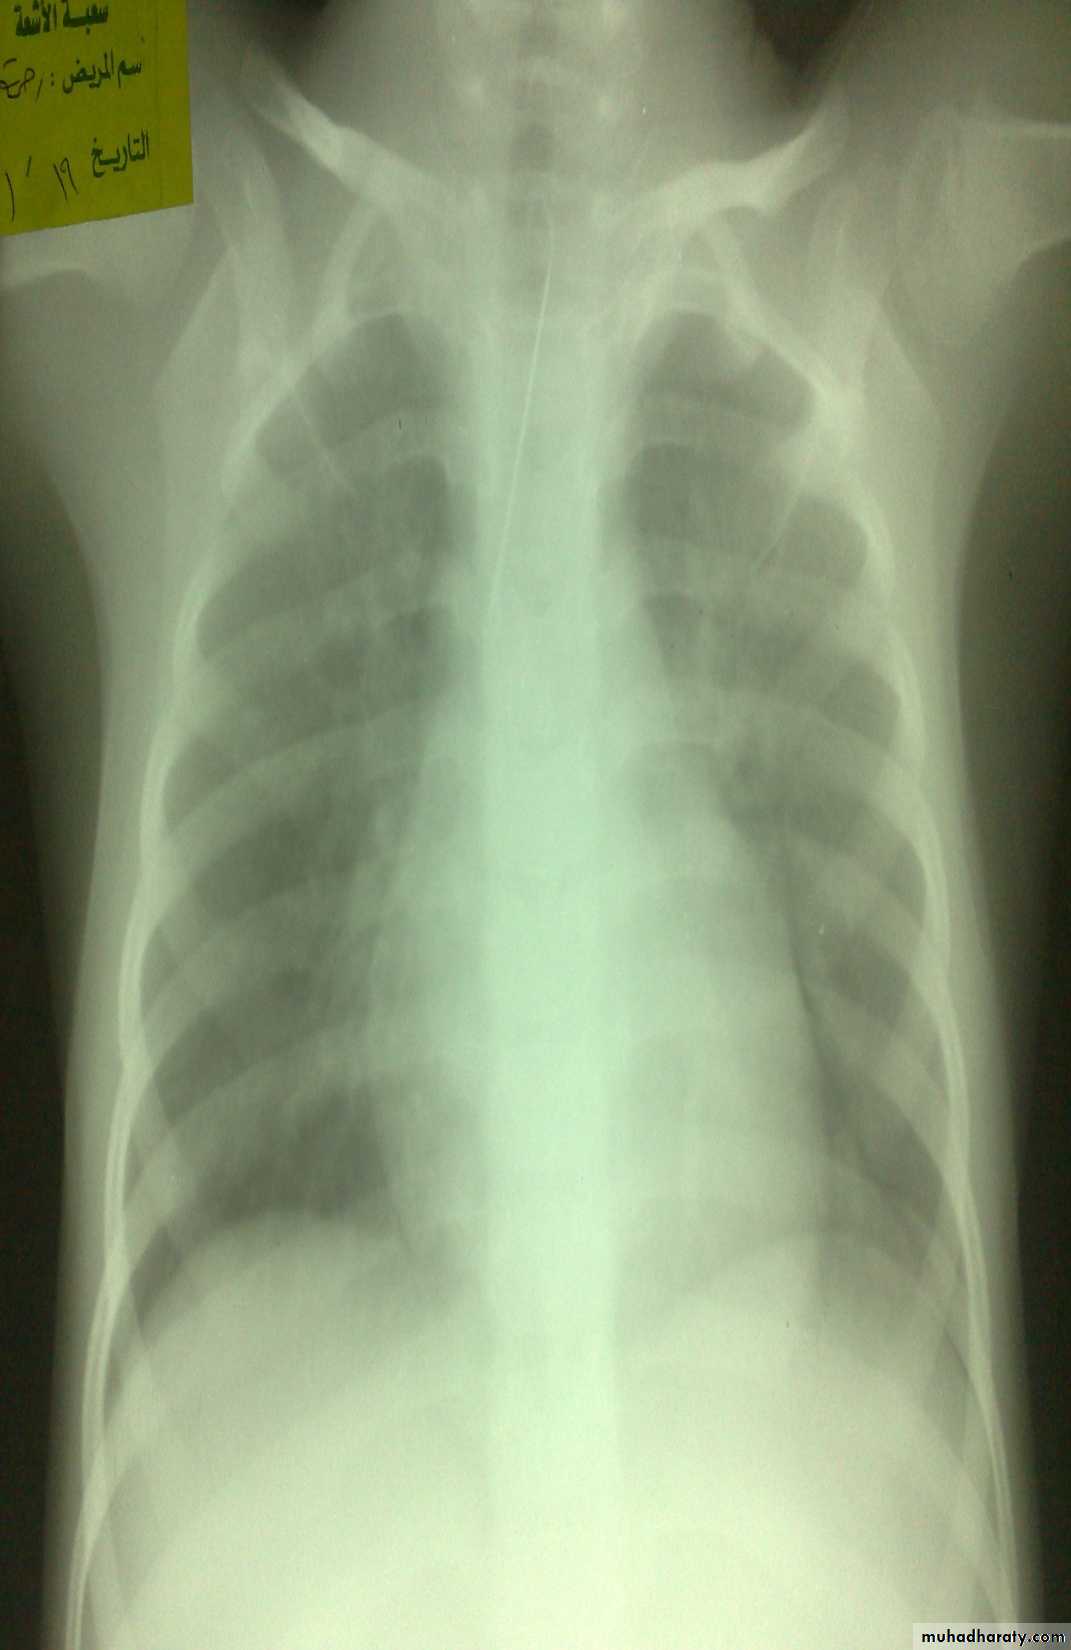

Diagnosis: achalasia cardia

Presentation:• Hailtosis

• Vomiting (not projectile)

• Wheezing

• Chest infection

Ba-swallow dilatation of esophagus with narrowing of lower part.

Treatment cardiomyotomy